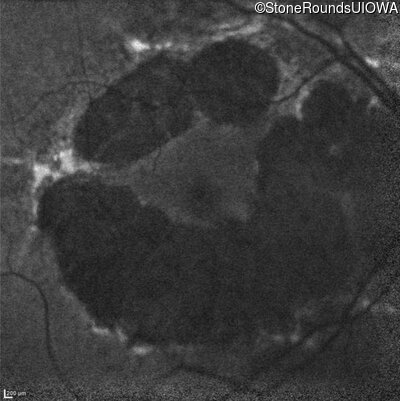

Blue Autofluorescence - Right - 20/32

Exemplar